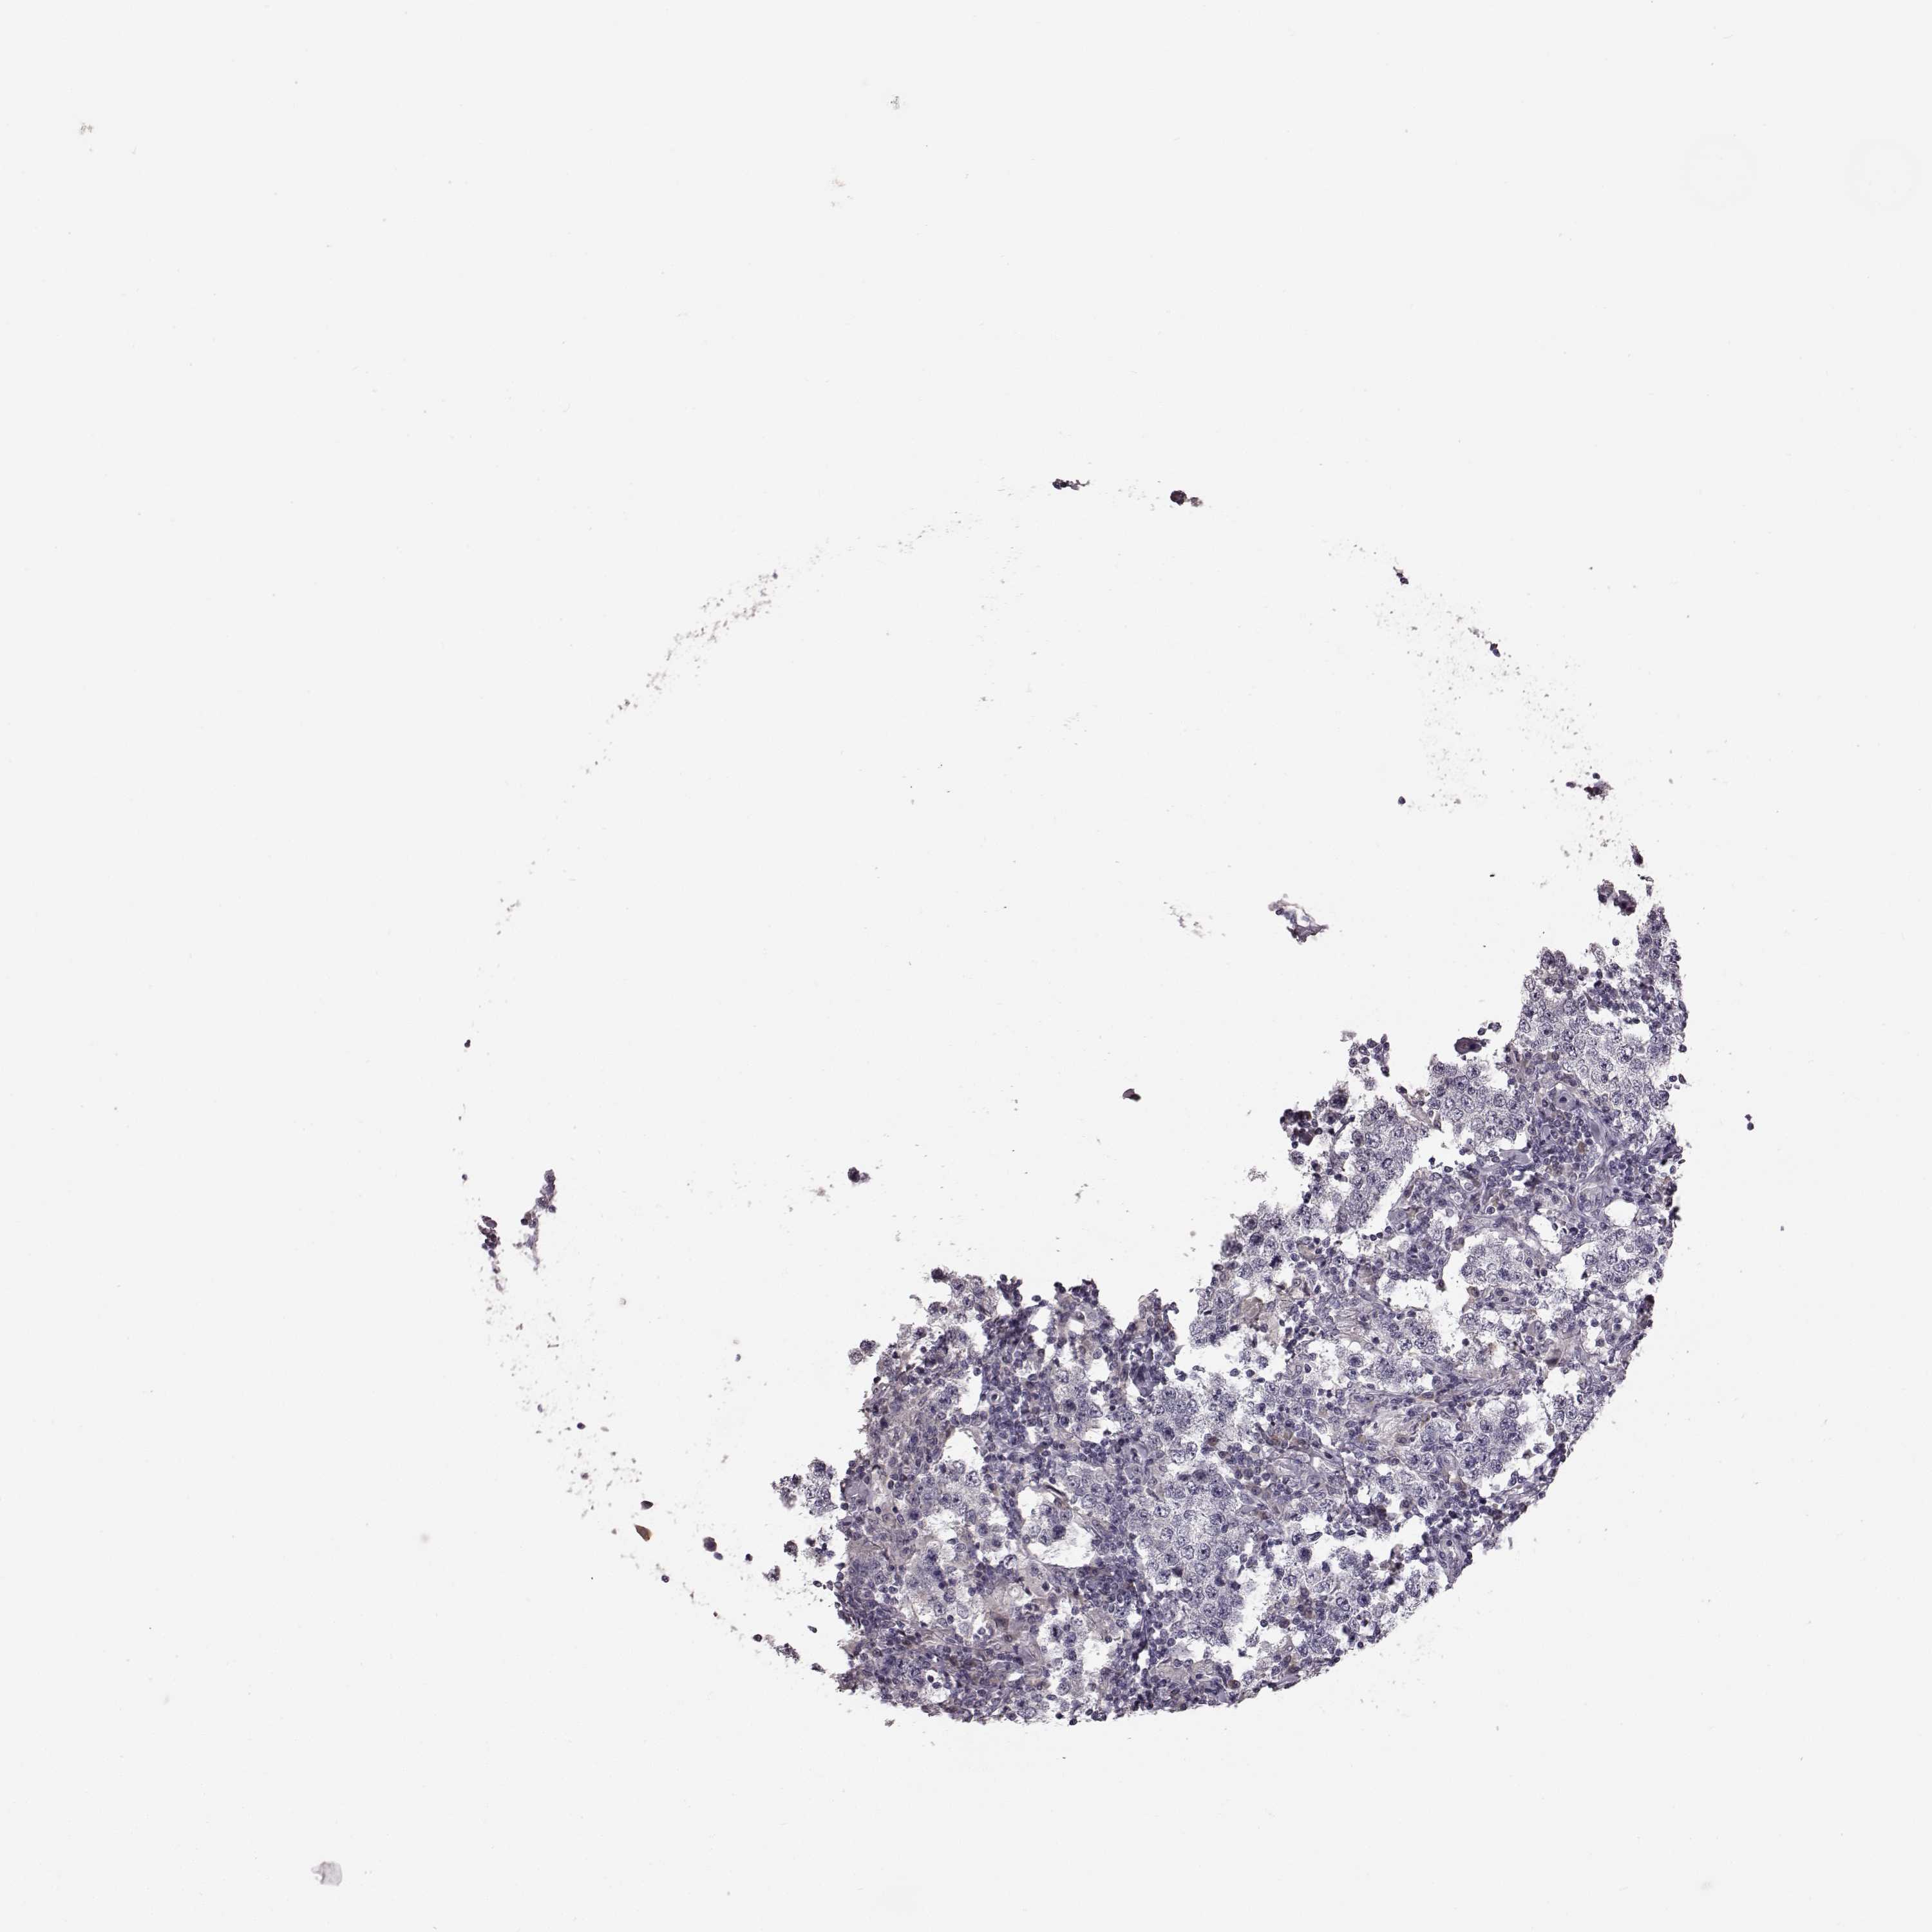

TESTIS CANCER - Protein expressioni

A mouse-over function shows sample information and annotation data. Click on an image to view it in a full screen mode. Samples can be filtered based on level of antibody staining by selecting one or several of the following categories: high, medium, low and not detected. The assay and annotation is described here.

Note that samples used for immunohistochemistry by the Human Protein Atlas do not correspond to samples in the TCGA dataset.

Antibody stainingi

Antibody staining in the annotated cell types in the current human tissue is reported as not detected, low, medium, or high, based on conventional immunohistochemistry profiling in selected tissues. This score is based on the combination of the staining intensity and fraction of stained cells.

Each image is clickable and will lead to virtual microscopy that enables deeper exploration of all samples and also displays staining intensity scores, fraction scores and subcellular localization as well as patient and tissue information for each sample.

Antibody HPA042369

Staining

High

Medium

Low

Not detected

Intensity

Strong

Moderate

Weak

Negative

Quantity

>75%

75%-25%

<25%

None

Location

Nuclear

Cytoplasmic/membranous

Cytoplasmic/membranous,nuclear

Seminoma, NOS

Carcinoma, Embryonal, NOS

Teratoma, malignant, NOS